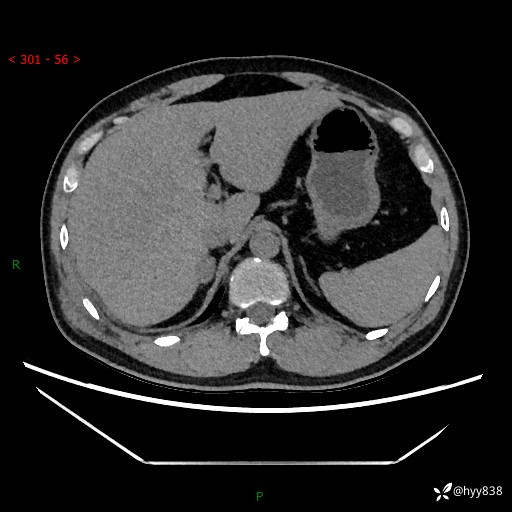

现病史:患者9月4日摔伤在深圳市宝安区中心医院行CT检查提示右侧肾上腺区结节(38*27mm),复查B超提示右侧肾上腺区可见一61*24mm异常低回声团,建议进一步检查。进一步完善增强CT后提示:右侧肾上腺区肿块及周围渗出改变,大致同前,考虑肾上腺腺瘤,不除外瘤内出血可能,否认阵发性头晕、头痛、出汗、乏力等不适,门诊以“ 右侧肾上腺肿瘤”收入住院。 起病来,患者精神、食欲、睡眠可,大便通畅,小便如上述,体力体重无明显改变。

肾上腺CT平扫

增强(动脉期+静脉期)